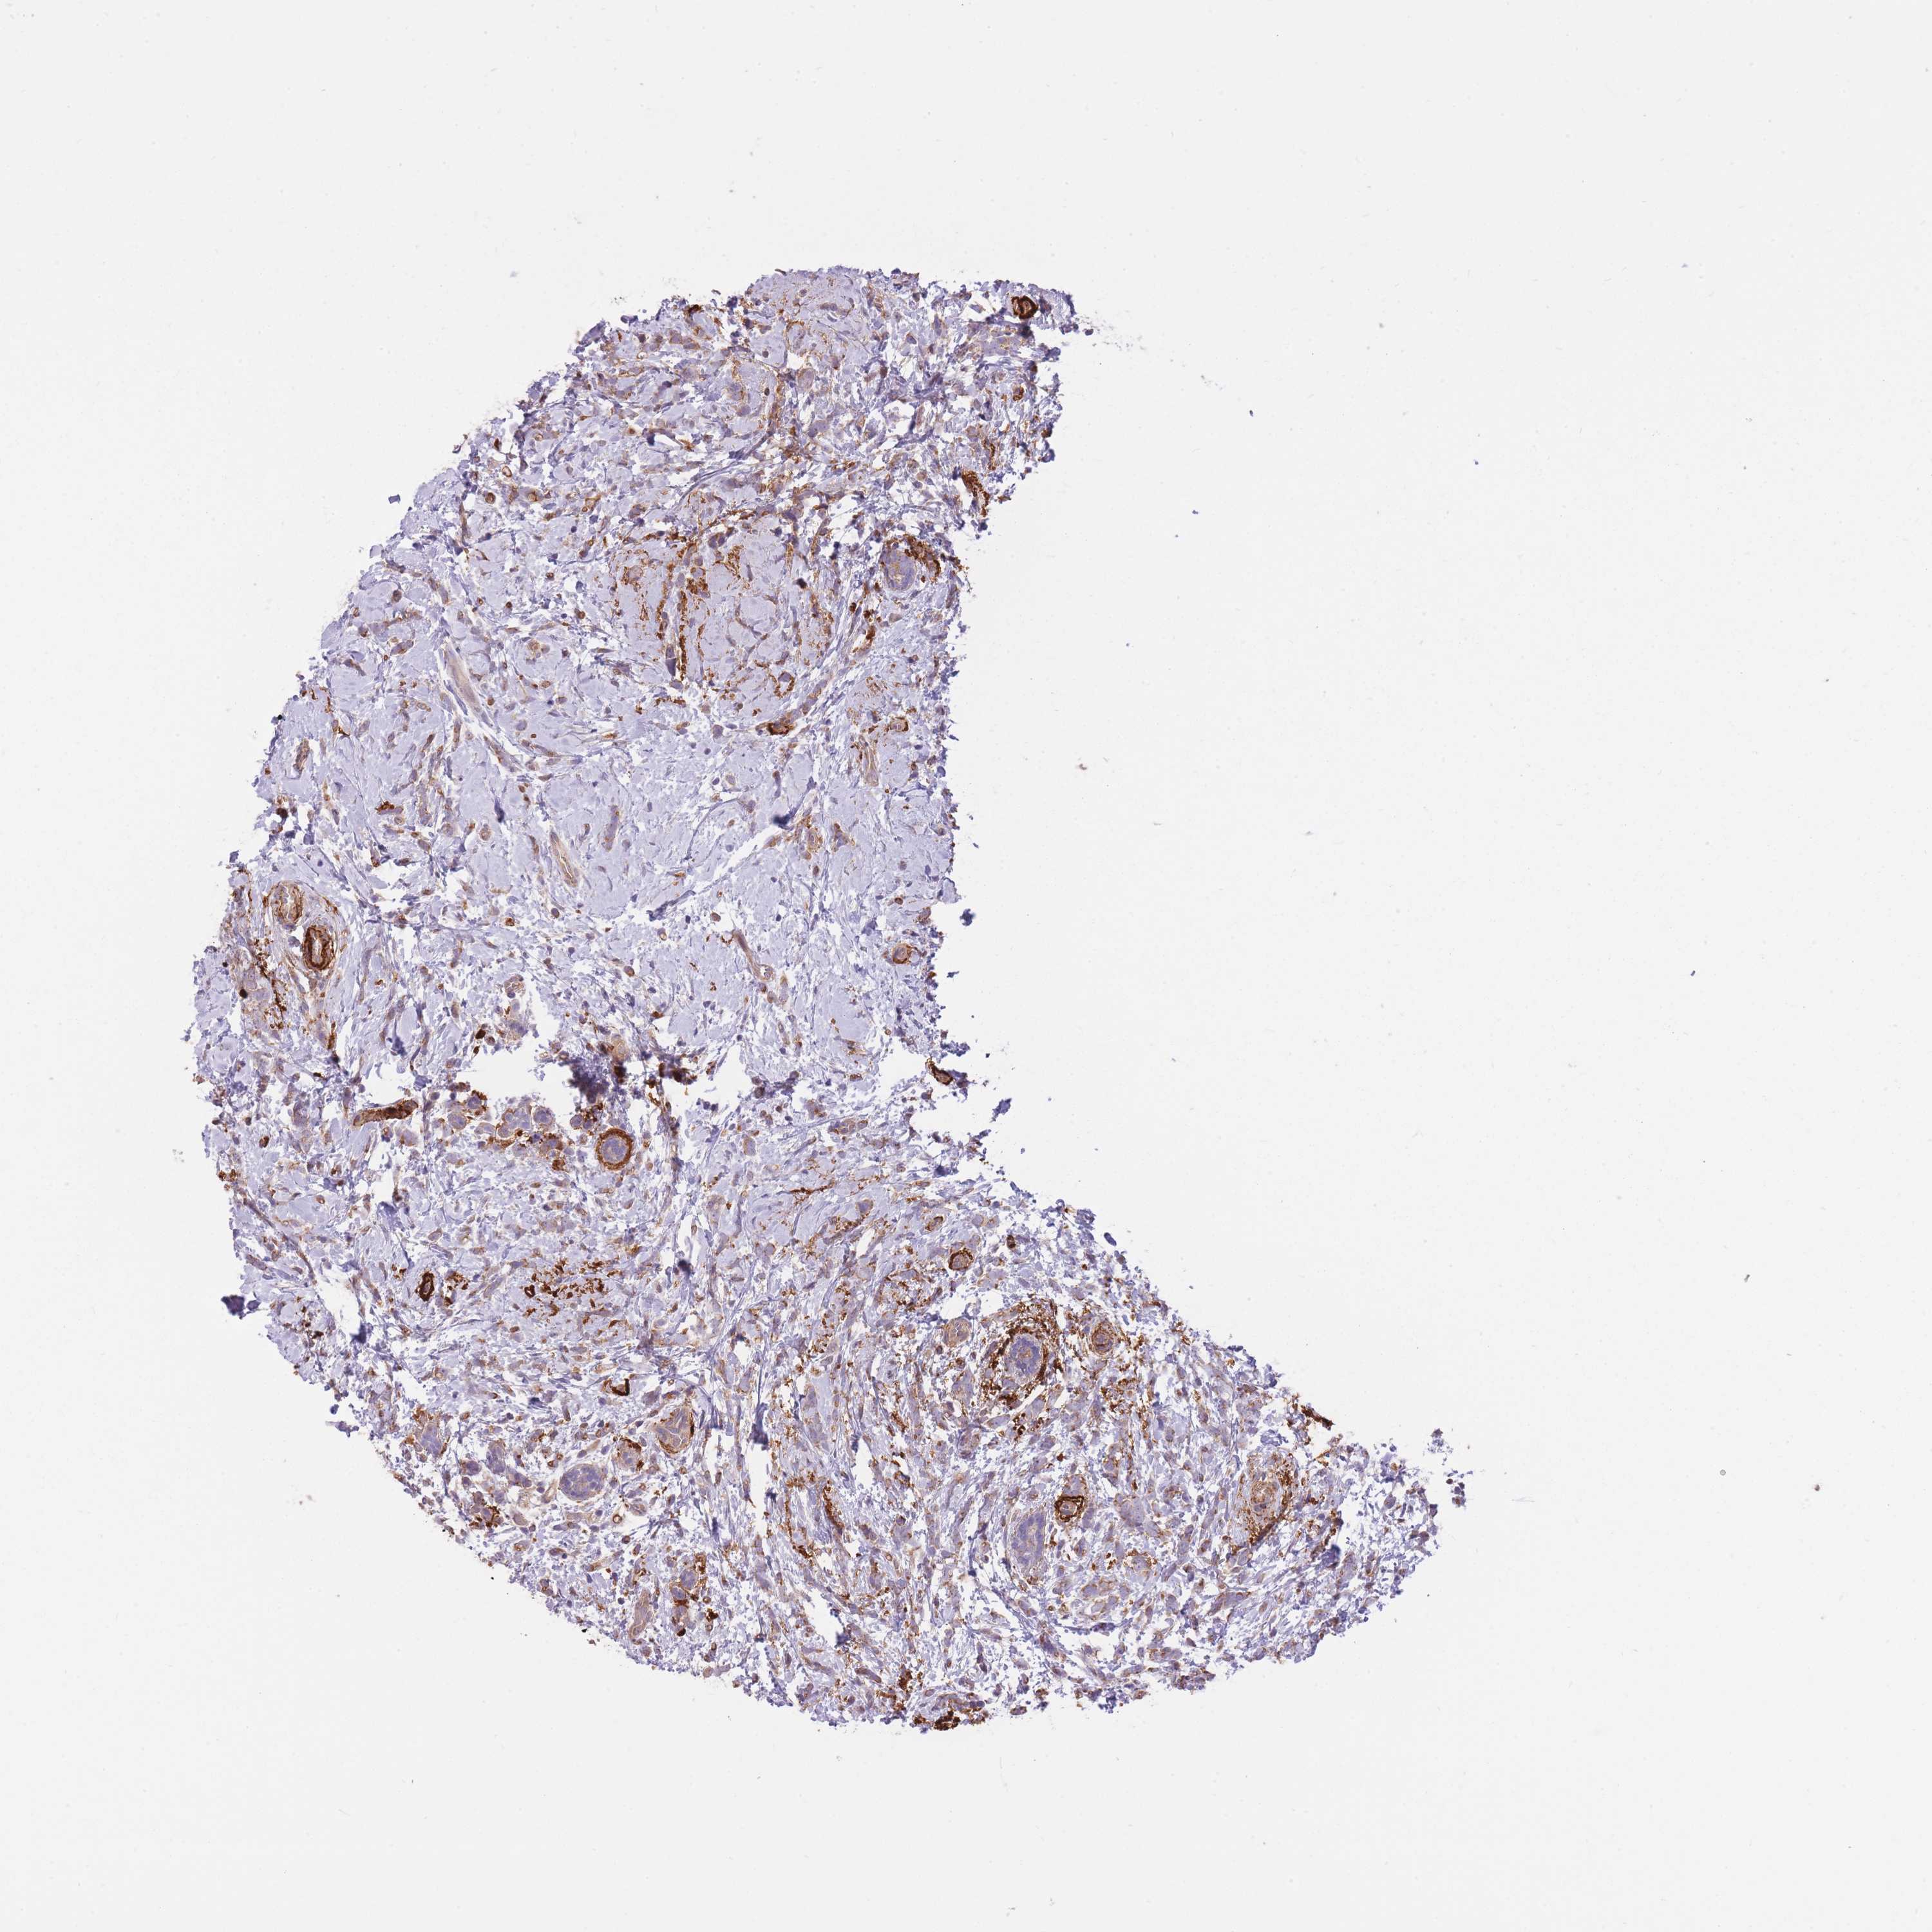

CANCER BREAST CANCER Show tissue menu

BRCA TCGA BRCA VALIDATION PROTEIN EXPRESSION